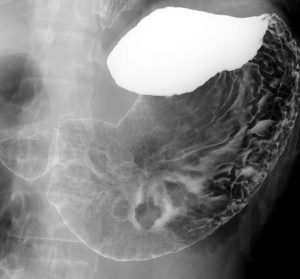

胃癌をしっかり表そう! 胃X線撮影法 虎の巻〜撮影手技を基本から応用まで段階的にマスターできる! - 羊土社。

好きです: 400

胃X線検査の撮影方法・画像の見方 - 第1種放射線取扱主任者試験対策。

好きです: 69

好きです: 415